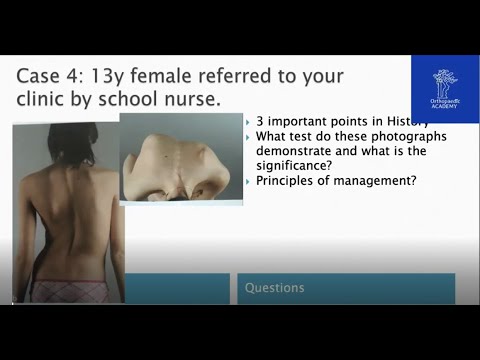

Cours FRCS en Ligne - Examens Cliniques et de...

Ce cours est enregistré à partir du cours « Discussions de cas pour les examens orthopédiques ».Pour les webinaires et cours à venir, veuillez visiter : www.OrthopedicAcademy.co .uk. Veuillez...

Orthopaedic Academy

institution commerciale